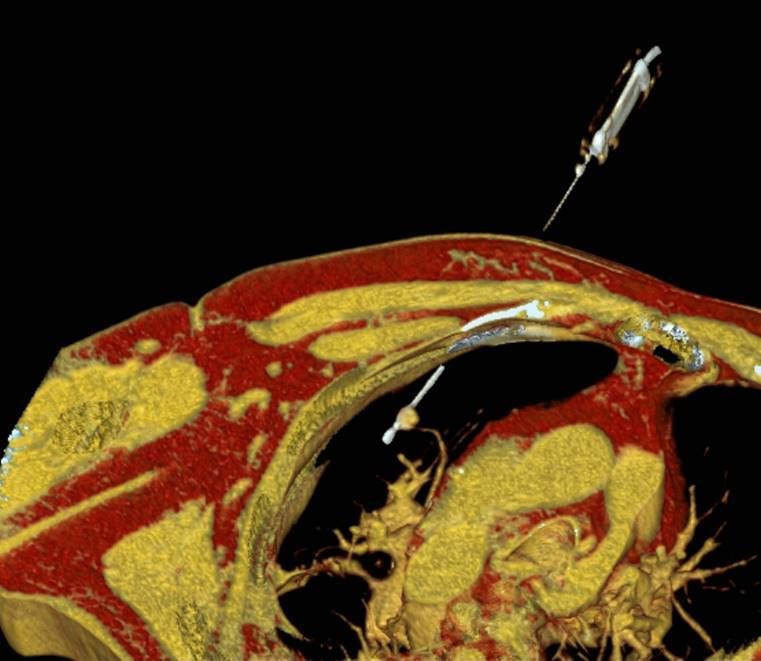

Die minimalinvasive Thermoablation ist auch eine Therapieoption für Lungentumore. Damit ein Lungentumor mit diesem Verfahren effektiv und sicher behandelt werden kann, sollten bestimmte Bedingungen (wie Größe, Anzahl und Lage) erfüllt sein. Ob diese Voraussetzungen gegeben sind, wird das Vorgehen vor der Therapie mit Kollegen aller für diese Fragestellung relevanten Fachdisziplinen besprochen.

Abbildung: Bei der perkutanen Thermoablation von Lungentumoren werden spezielle Applikatoren unter CT-Bildgebung in den Zieltumor eingebracht. Durch Hitze wird der Tumor dann zerstört.